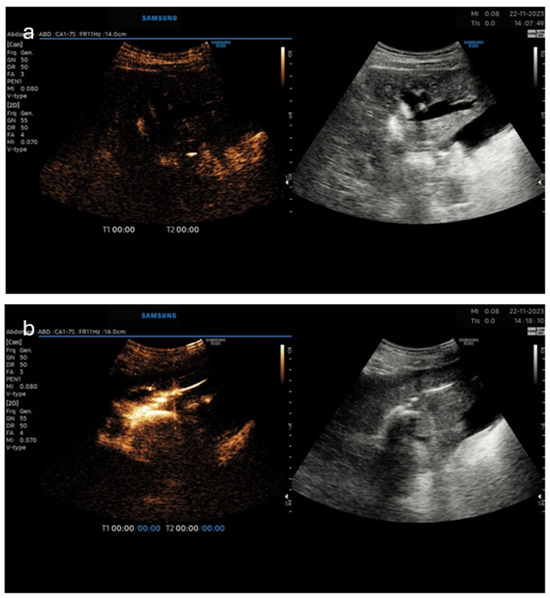

Figure 2. (Dual image—left CEUS image, right—B-mode). Panel (a)—prior to US contrast injection demonstrating markedly dilated intrahepatic bile ducts in the left liver lobe; panel (b)—biliary decompression and filling of the biliary catheter and bile ducts after US contrast injection.

The first case was a palliative PTCD in a patient with terminal-stage gallbladder cancer that spread into the intrahepatic bile ducts (Figure 2). An 8 Fr pigtail catheter was inserted in the left liver lobe for biliary decompression. Three months later, the patient presented with a non-functioning PTC drain. Due to the fact that the injection of a diluted US contrast agent (SonoVue) was initially impossible, a higher pressure on the syringe’s plug was exerted. A possible clot was the reason for the obstruction of the drainage tube, which was overcome. Then the diluted US contrast agent entered the biliary ducts unhindered and confirmed the proper position of the patent drainage tube.